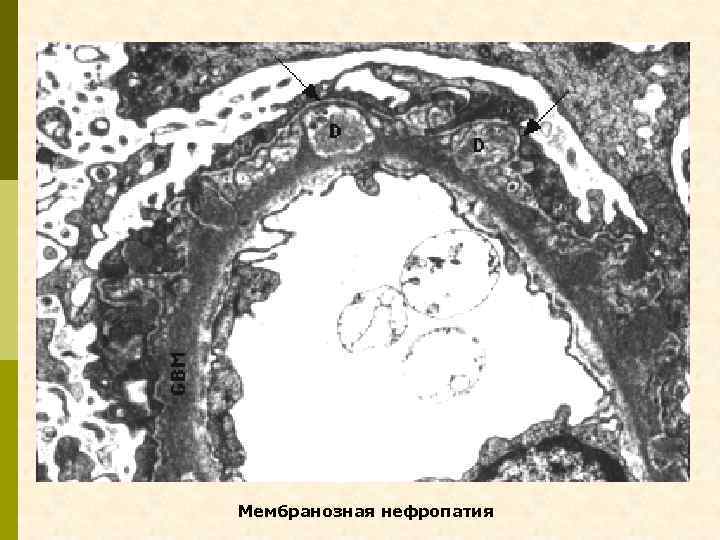

Электронноплотные (темные) депозиты на эпителиальной поверхности ГБМ (субэпителиальные). Каждый из них отделен друг от друга, а некоторые включены в вещество, подобное ГБМ (II–III стадия мембранозной нефропатии). Малые ножки подоцитов сливаются между собой.

СТАДИИ МЕМБРАНОЗНОЙ НЕФРОПАТИИ по Zollinger и Minatsch (1978) 1 Субэпителиальные иммунные депозиты без каких-либо изменений ГБМ 2 Образование шипов (выступы ГБМ) 3 Включение депозитов в ГБМ, что делает её утолщенной 4 Стадия восстановления; ГБМ нерегулярно утолщена, не содержит электронноплотных депозитов или лакун 5 Капиллярный коллапс и гломерулярный склероз с сегментарными полулуниями 6 Новообразованные субэпителиальные депозиты и «шипы» в сегментарно склерозированных клубочках, как признак обострения мембранозной нефропатии Zollinger HU, Minatsch MJ. Renal Pathology in Biopsy, Springer, Heidelberg, 1978

Мембранозная нефропатия